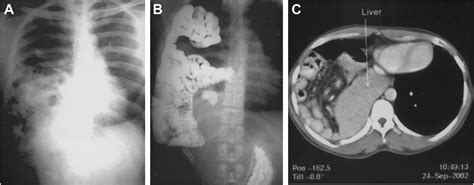

Chest X-ray: Provides a basic view of the chest and can show the presence of a hernia.

CT Scan: Offers detailed images of the chest and abdomen, helping to identify the location and size of the hernia.

MRI: Provides detailed images of soft tissues and can help identify the hernia and its effects on surrounding structures.